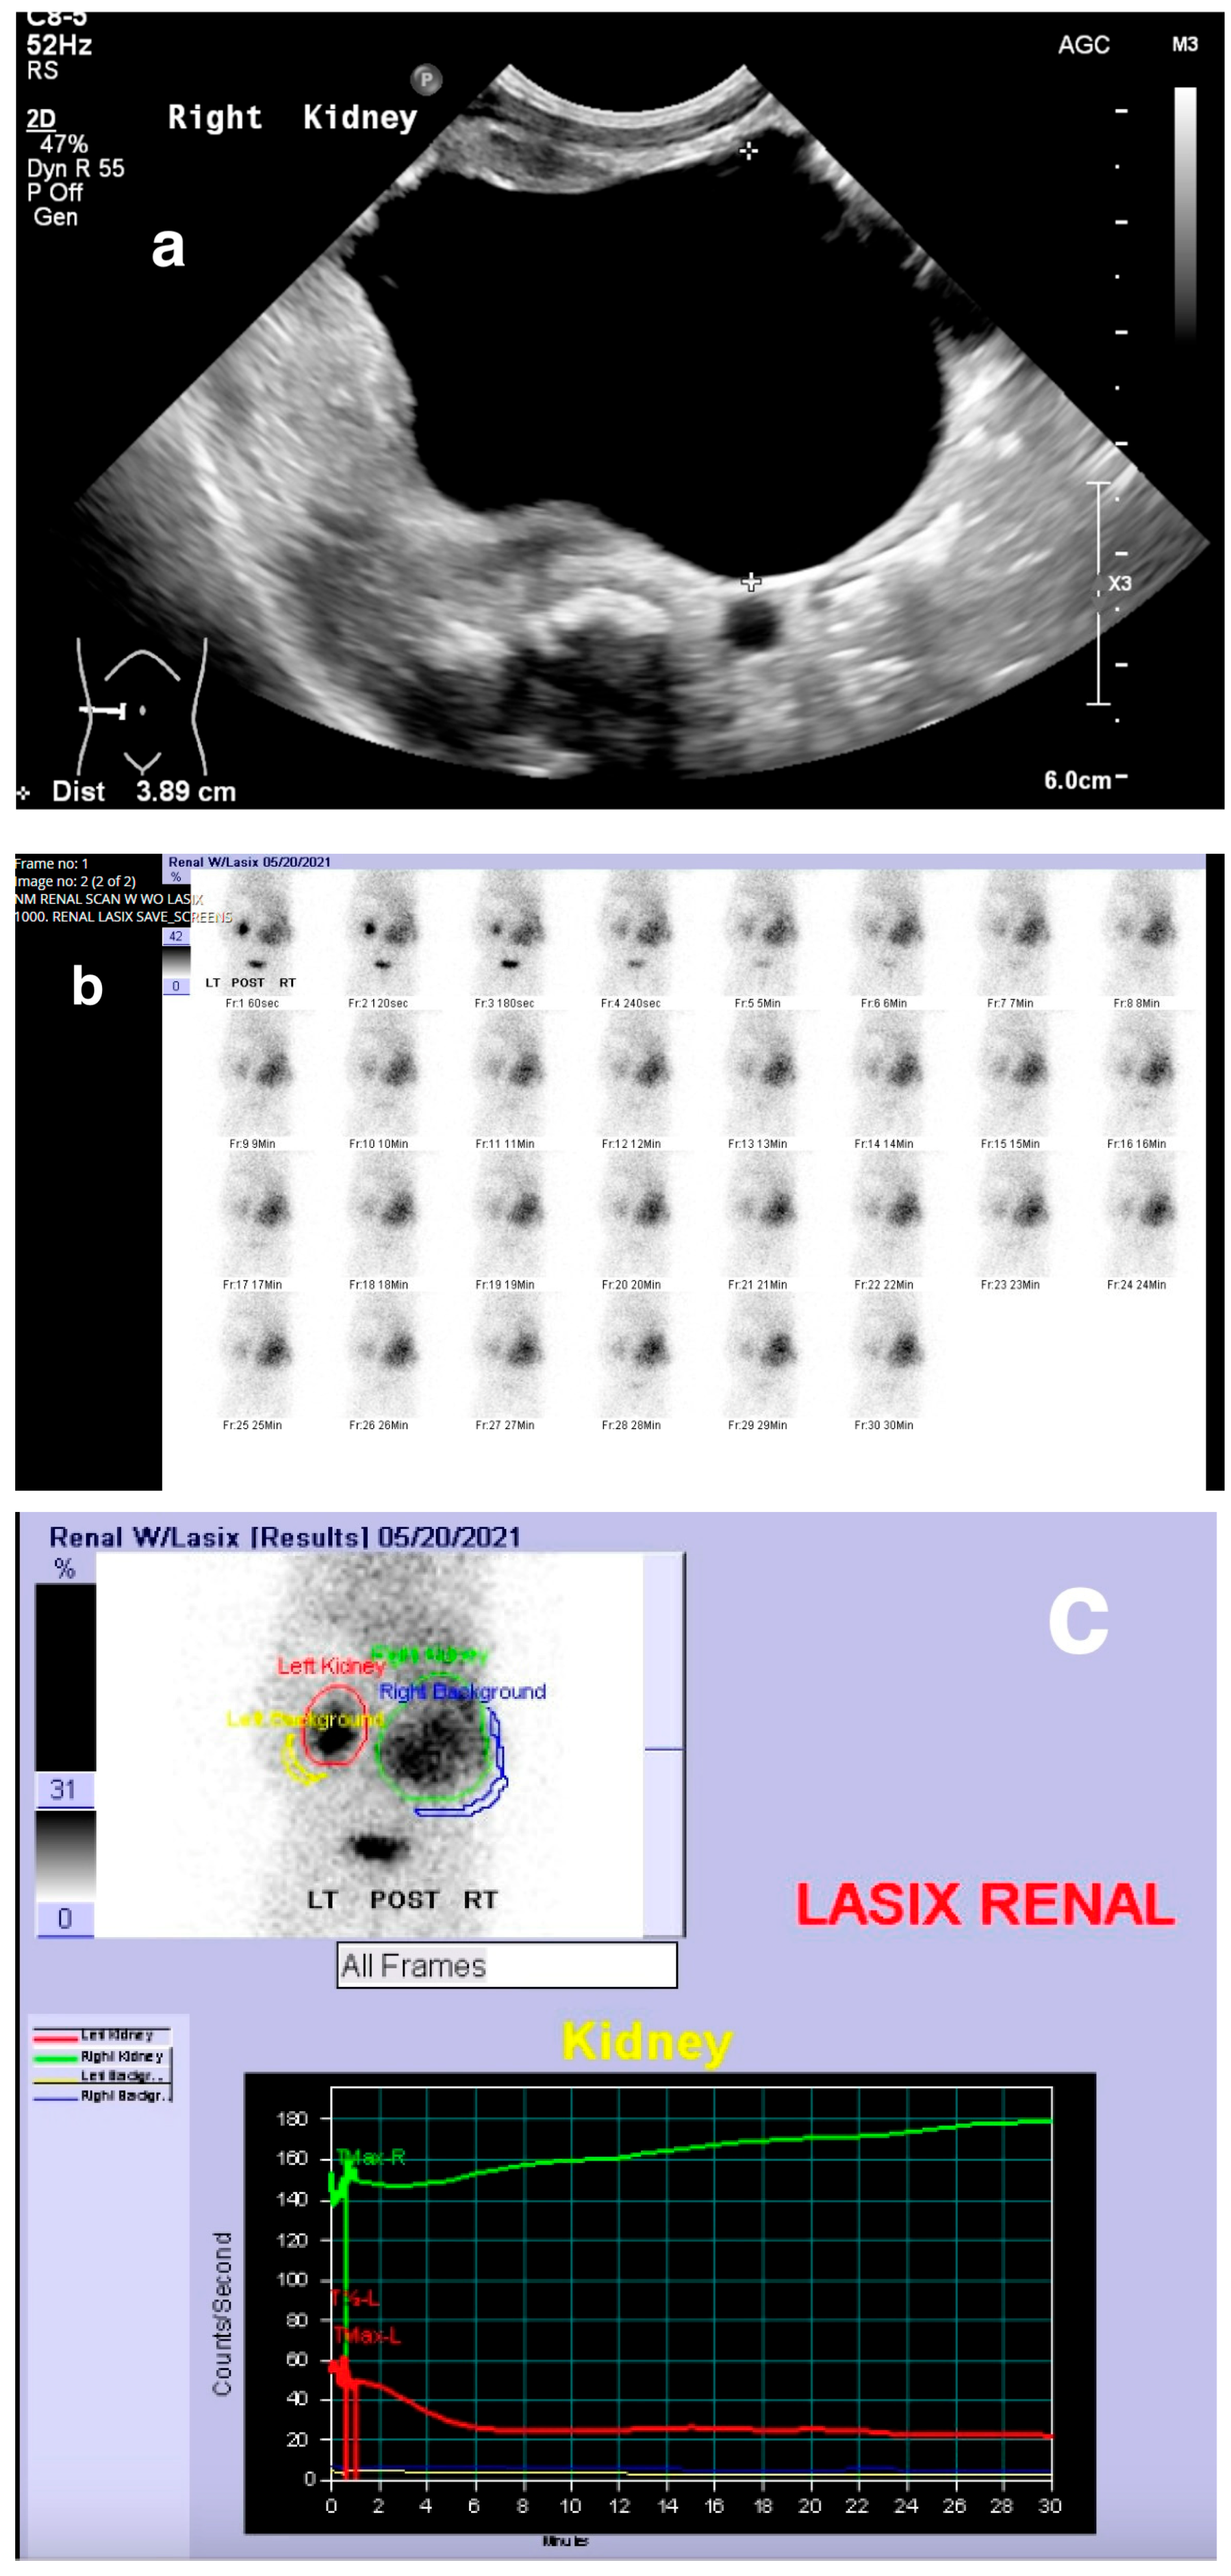

Obstruction at the ureteropelvic junction (UPJ) is a common congenital urinary tract obstruction. It is often diagnosed via antenatal ultrasound (US), which can reveal significant pelvic and calyceal dilation. Postnatally, UPJ obstruction can be detected using US, CT, or MRI, but dynamic nuclear medicine remains the gold standard for diagnosis (Figure 10 and Figure 11).

Figure 10. Right ureteropelvic junction obstruction in a neonate. (a) US shows severe dilatation of the right renal pelvis. (b) Nuclear medicine shows retention of radiotracer in the right kidney. (c) Mild drainage occurs in the right kidney after Lasix, with a T ½ exceeding 30 min.

Medicina 61 00696 g010